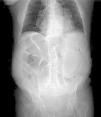

Varón de 82años con distensión y dolor abdominal generalizado, acompañado de vómitos oscuros de aspecto retencionista y deposiciones diarreicas. En radiografía simple de abdomen (fig. 1) existe aire en pared gástrica y dilatación de asas intestinales, por lo que se solicita TC abdominal (fig. 2) donde se observa gas intramural asociado a dilatación gástrica, neumoperitoneo (fig. 3) y gas en vena porta (fig. 4). Se realiza laparotomía exploradora y se observa un estómago distendido con burbujas de gas en su serosa, sin signos de necrosis transmural ni perforación. La gastroscopia intraoperatoria muestra una mucosa necrótica-ulcerada sin sangrado espontáneo en cara posterior, cuerpo y curvatura mayor. Dados estos hallazgos se opta por no realizar ningún acto quirúrgico más. Se aísla Lactobacillus jensenii en hemocultivos y se trata con meropenem+linezolid. El paciente evoluciona favorablemente con mejoría en TC abdominal de control, recibiendo el alta hospitalaria. La gastritis enfisematosa es una patología rara producida por la translocación de microorganismos productores de gas dentro de las paredes gástricas. Hasta en un 42.4%1 de los casos no es posible aislar el causante y conlleva una mortalidad de hasta el 60%2. El TC es la prueba diagnóstica de elección, siendo fundamental el diagnóstico precoz y un tratamiento de soporte vital con antibioterapia de amplio espectro. Se reserva la cirugía cuando existe falta de respuesta al tratamiento conservador, sepsis severa o perforación gástrica3.